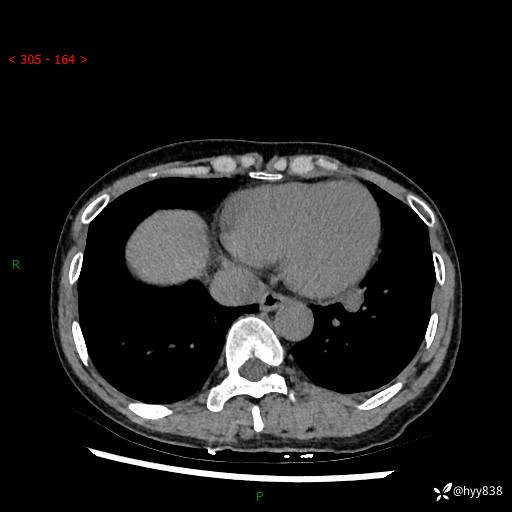

【患者信息】:55岁/女

【主诉】:咳嗽咳痰半月,发现肺占位2天

【现病史及既往史】:患者半月前出现咳嗽咳痰,伴头晕胸闷、无发热气喘。于当地医院住院行抗感染治疗1周(具体药物不详),后咳嗽减轻,但仍未完全缓解,复查胸部CT示:左肺下叶1.8*1.2结节软组织影。为求进一步诊治来我院,门诊以“肺占位”收入院。 自患病以来,精神、饮食、睡眠尚可,大小便正常,体力体重无明显减少。

【检查】:胸部CT平扫+增强

各期CT值:40hu 57hu 49hu